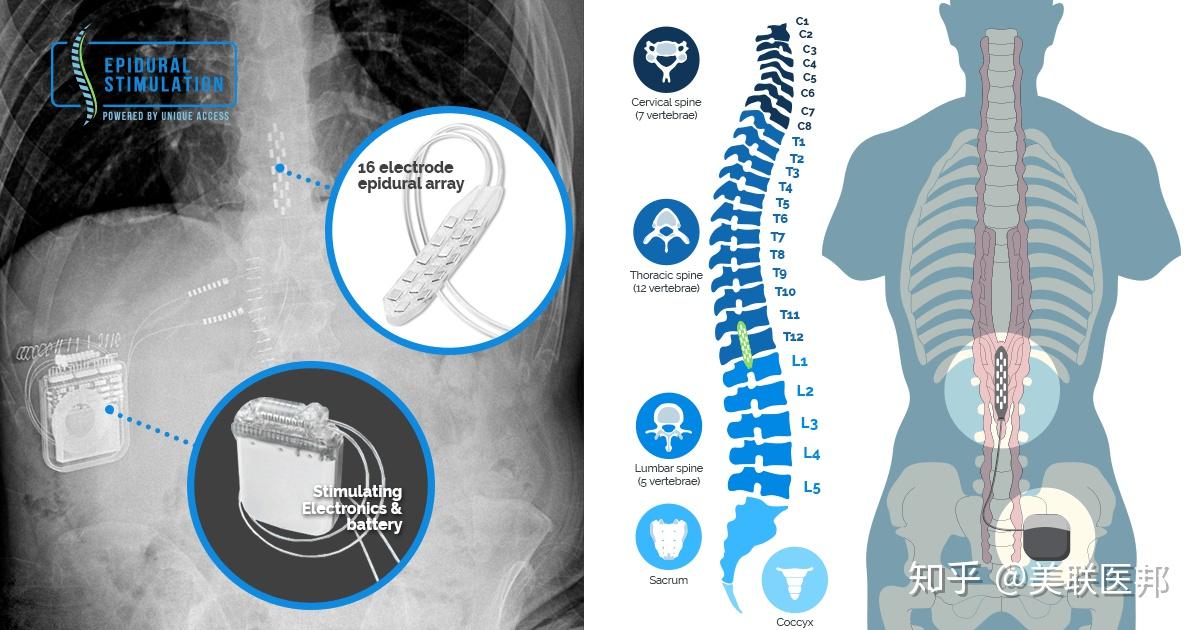

- 电刺激设备:这些复杂的设备使用电刺激来诱发动作。它们通常被称为功能性电刺激系统,它们使用电刺激器来控制手臂和腿部肌肉,以使脊髓损伤的人站立、行走、伸展和抓握。

脊髓损伤电刺激治疗技术

https://www.zhihu.com/video/1042814354436947968

脊髓损伤电刺激治疗技术

https://www.zhihu.com/video/1042814354436947968

脊髓损伤突破性进展报道

https://www.zhihu.com/video/1042817818013724672

脊髓损伤突破性进展报道

https://www.zhihu.com/video/1042817818013724672

脊髓损伤突破性进展报道

https://www.zhihu.com/video/1042817048316985344

脊髓损伤突破性进展报道

https://www.zhihu.com/video/1042817048316985344